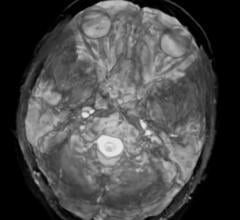

For the first time, researchers have confirmed an association between a common magnetic resonance imaging (MRI) contrast agent and abnormalities on brain MRI, according to a new study published online in the journal Radiology. The new study raises the possibility that a toxic component of the contrast agent may remain in the body long after administration.